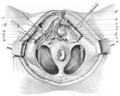

Dissection of female perineum, showing superficial blood-vessels and nerves